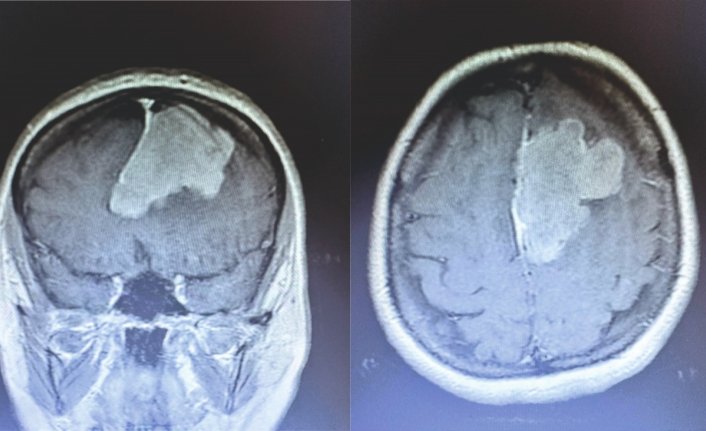

Tokat'ın Erbaa ilçesinde beyin tümör ameliyatı gerçekleştirildi.

Polat'ın nöronavigasyon eşliğinde mikroskopik yaklaşımla beyin tümörü ameliyatı, Erbaa Devlet Hastanesinde yapıldı.

Hastanede ikinci kez yapılan ameliyat, beyin ve sinir cerrahisi uzmanı operatör Dr. Ali Kalpan tarafından gerçekleştirildi.    TOKAT (AA)